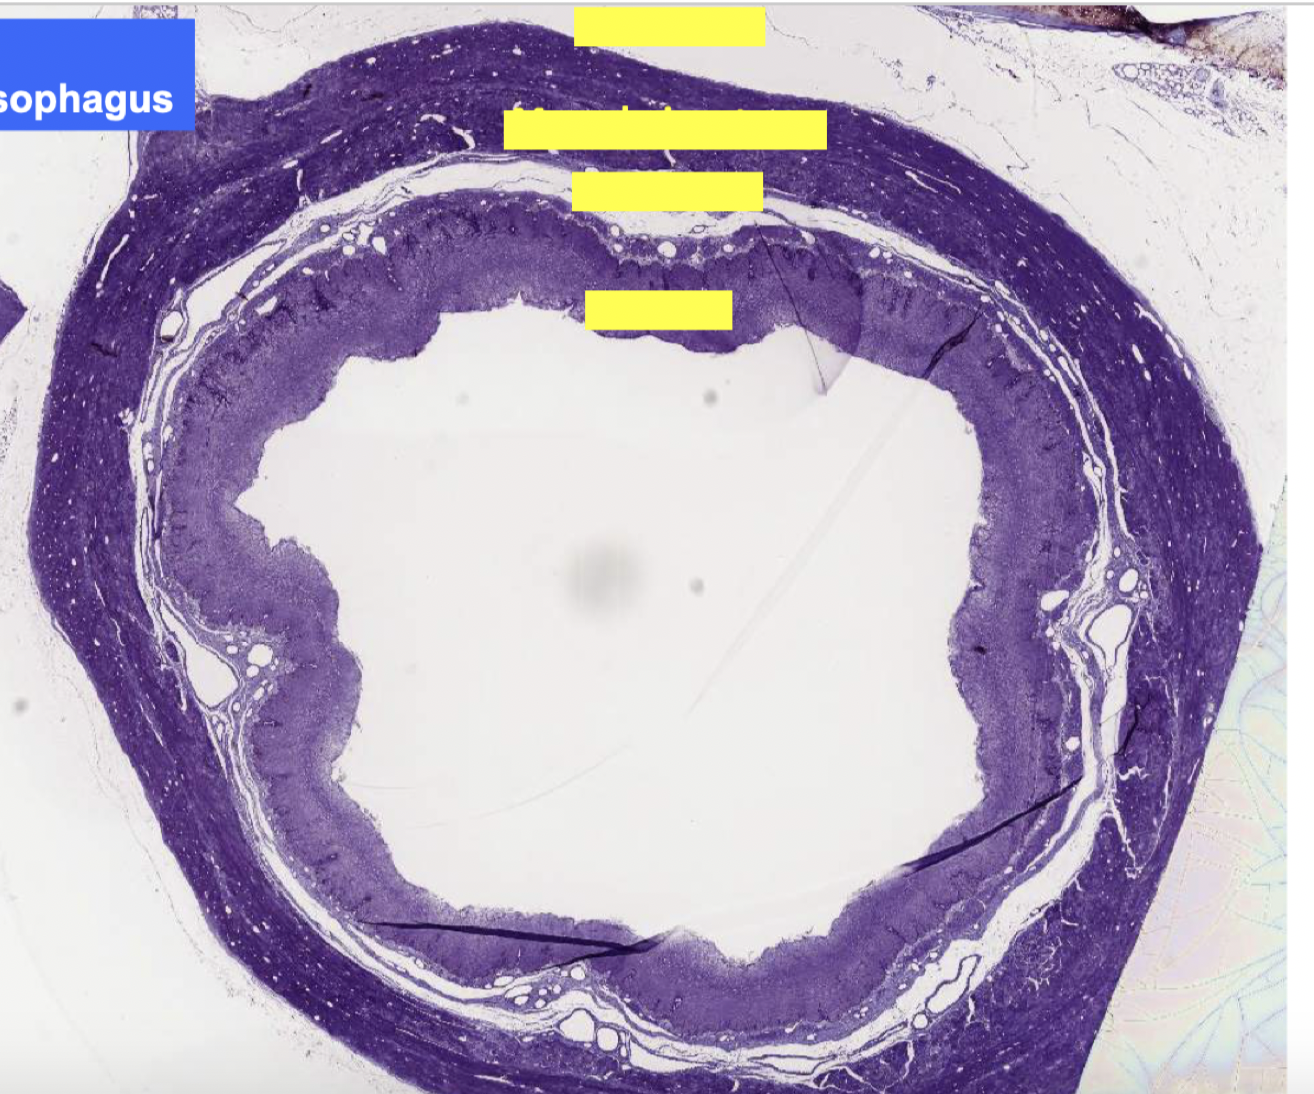

organization of tissue layers of GI tract

mucosa composed of

muscularis mucosae

what is lamina propria

what is muscularis mucosae